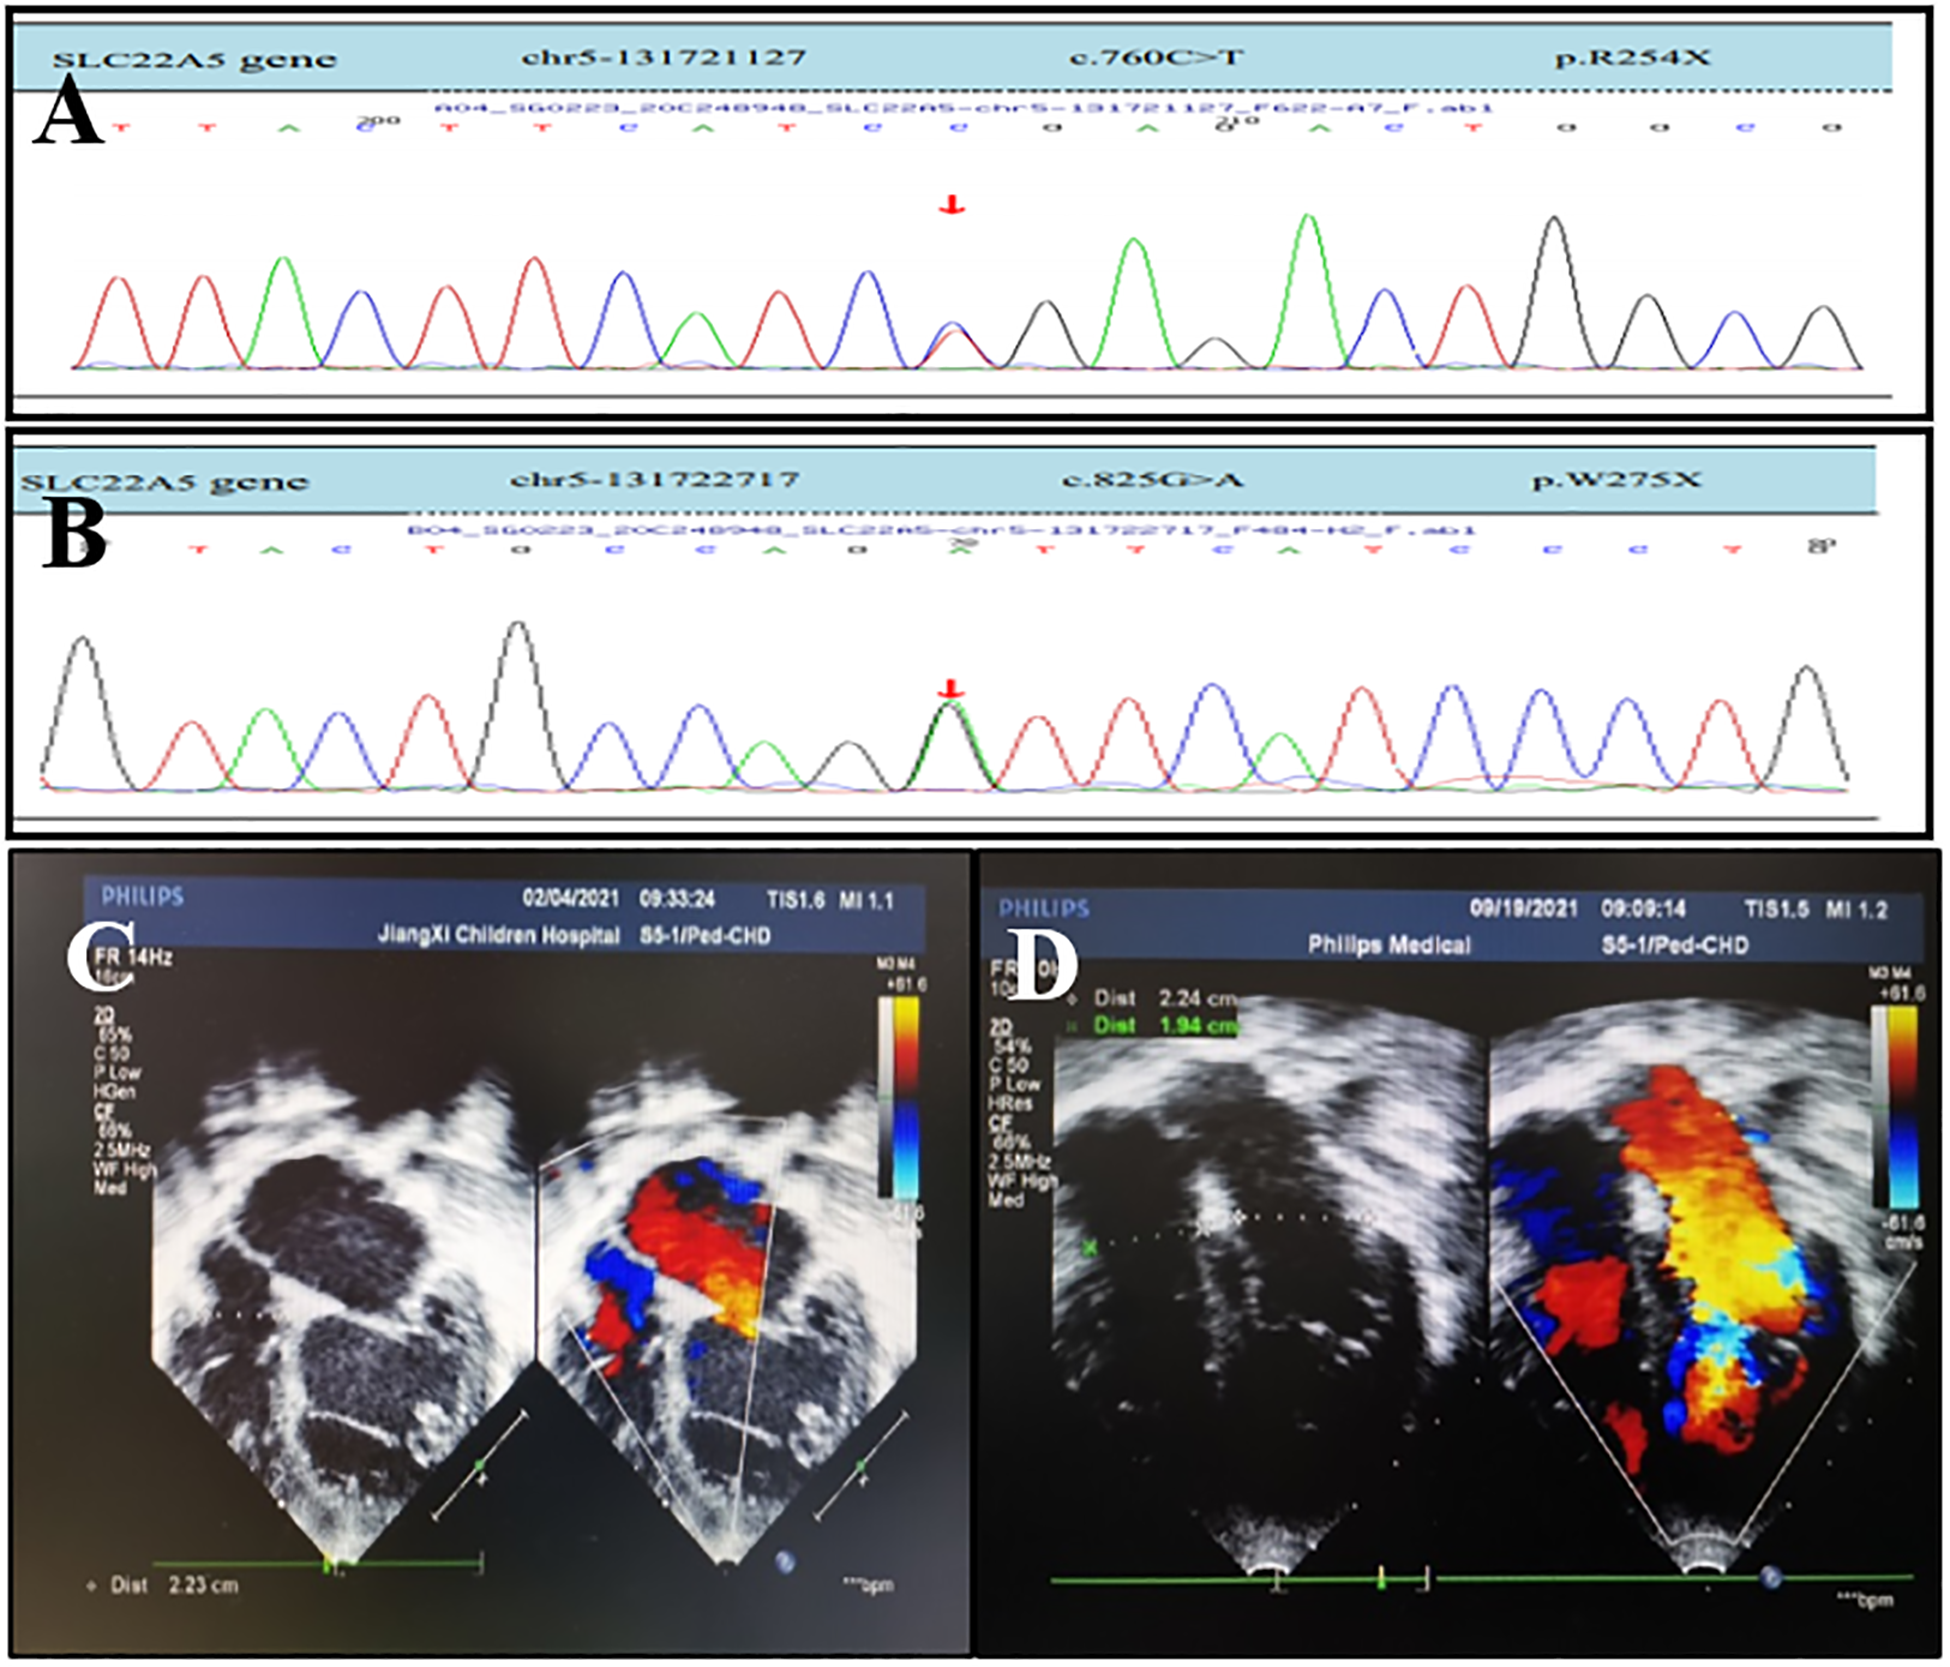

Figure 2

OCTN2 mutations and echocardiography of a 6-year-and 4-month-old boy (the proband's brother) with primary carnitine deficiency. (A) Mutation [c.760C > T (p.R254X)] in the SLC22A5 gene. (B) Mutation [c.825G > A (p.w275X) ] in the SLC22A5 gene. The arrows indicate the site of the mutation. (C) Transthoracic echocardiography (TTE) of the boy was performed in February 2021 when he was 6 years and 4 months old and did not receive treatment. (D) TTE of the boy after 6 months of treatment in September 2021. TTE parasternal four-chamber view shows diameter changes of heart chambers before and after 6 months of treatment.

High-throughput sequencing was used to screen for mutations. Bioinformatics and clinical information analytics were used to analyze genetic data, and Sanger sequencing was used to confirm SLC22A5 mutations in the patient and his first-degree relatives. The results indicated compound heterozygous mutations in SLC22A5, including c.760C > T (p.R254X) and c.825G > A (p.w275X), inherited from the mother and father, respectively (Figures 2A,B; Table 3). Both parents are heterozygous carriers. The patient harbored the same mutations as the proband. Echocardiography and serum tandem mass spectrometry results were normal in the parents.